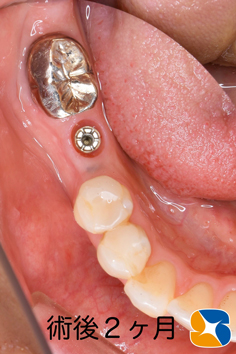

手術から2ヶ月後の状態です。綺麗に歯肉が整い、アゴ骨も回復しています。

最初の手術から3ヶ月強でインプラントの歯が完成しました。